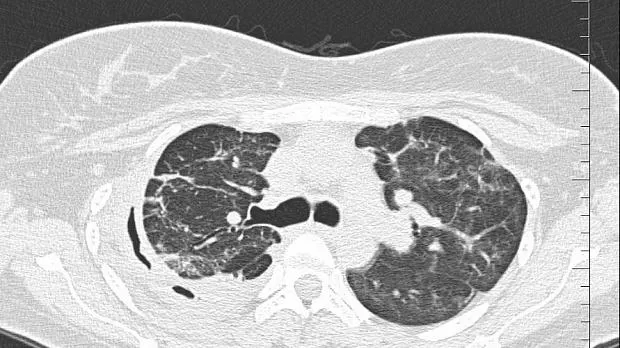

08.06.2020 проведена повторная установка блокатора в промежуточный бронх (блокатор Medlung №13) с хорошим клиническим эффектом (сброс воздуха по плевральному дренажу прекратился через 8 часов после вмешательства). Подтверждено данными Р-КТ органов грудной клетки.